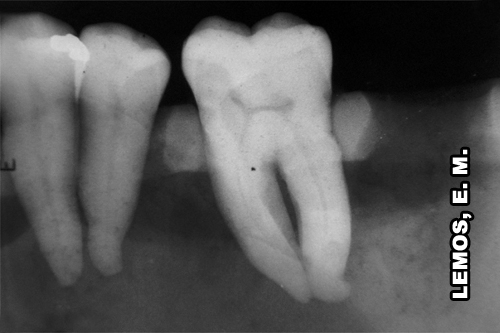

Observar o 2o. molar inferior esquerdo com a relação teto da câmara pulpar e assoalho diminuída, canais atrésicos e curvatura cervical e apical moderada, principalmente nos mesiais. |

Observar o 1o. pré-molar inferior direito com anatomia normal, 1o. molar apresenta câmara pulpar com volume normal com relação à distância teto da câmara pulpar e assoalho e ligeira curvatura cervical nos canais mesiais. 2o. molar invertido no sentido proximal, quando o correto seria um dente do lado oposto, apresenta câmara e canais radiculares atresiados, dificultando principalmente, o treinamento inicial. |